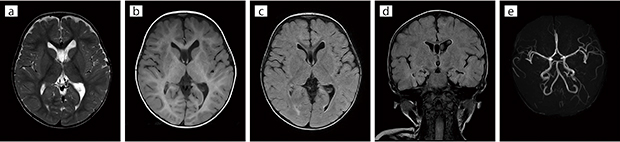

■臨床例1:小児頭部(Soft Sound ON)

小児(1歳)の頭部をSoft Soundで撮像。鎮静下で目覚めることなく撮像が可能であった。

スライス厚はa〜dは4mm,eは1.2mm。

a:T2 WI,AX

b:T1 WI,AX

c:FLAIR,AX

d:FLAIR,COR

e:3D-TOF MRA